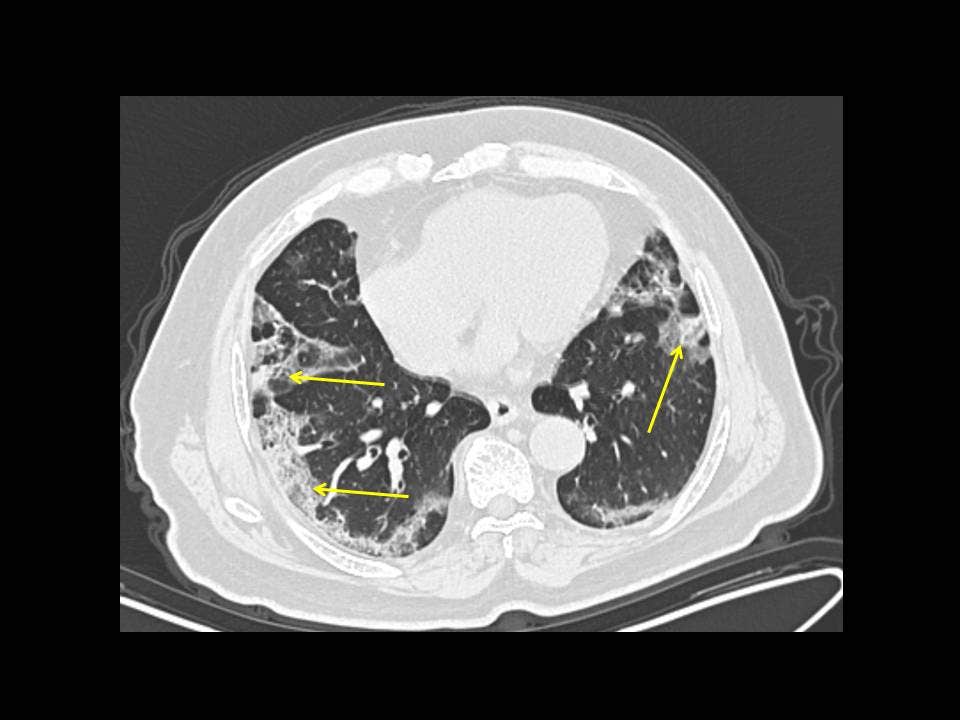

Фотографии и снимки КТ легких без контрастных веществ

Раздел: Визуальный дайджест